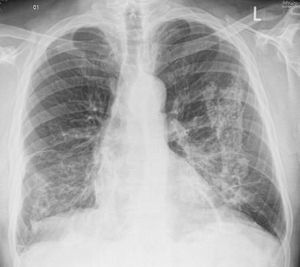

The above CXR refers to which occupational lung disease??

1.silicosis 2.pneumoconiosis 3.asbestosis 4.chronic Beryllium disease

Asbestosis

In my opinion - Pneumocoinosis